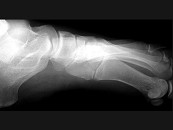

- 单项选择题女,25岁, 扭伤后足中部痛,结合图像, 最可能的诊断是 ( )

A、內侧楔状骨骨折

B、外侧楔状骨骨折

C、足舟骨骨折

D、中间楔状骨骨折

E、未见异常